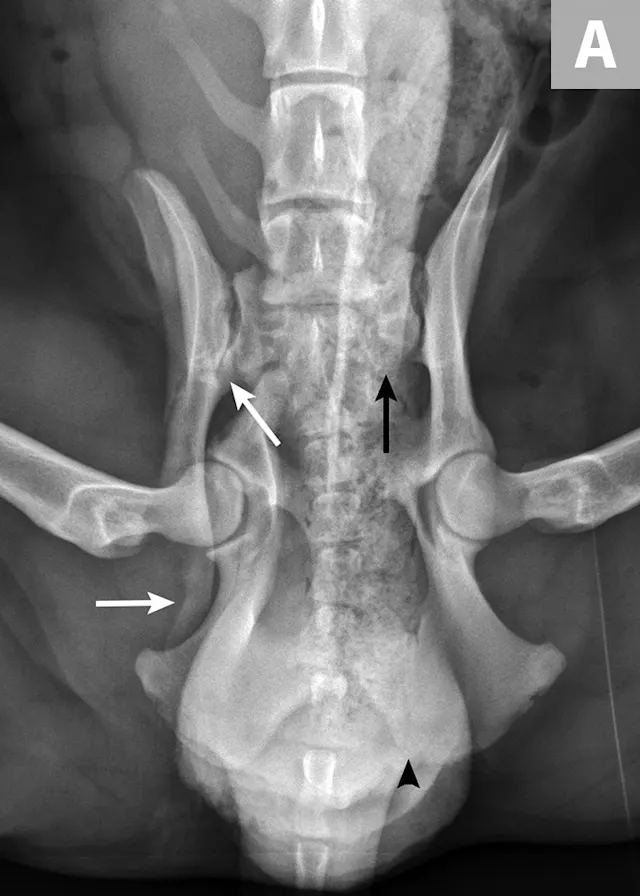

There are many different types of pelvic fracture configurations, and nearly half of pelvic injuries in dogs and cats involve fractures of the ilium.3,4,7,8 Clinically significant fractures involve the weight-bearing axis of the pelvis that includes the ilium and acetabulum (Figures 1-3). Although not a fracture, sacroiliac luxation is potentially significant because the sacroiliac joint is a component of the weight-bearing axis of the pelvis. Unilateral or bilateral fractures or luxations may occur, and it is common for patients to have a combination of pelvic injuries.3,4,7,13

Surgical management of pelvic fractures can be determined based on pet owner expectations and fracture configurations (Figures 4 and 5). Factors that influence surgical intervention include ≥45% narrowing of the pelvic canal; acetabular fractures involving the cranial two-thirds of the acetabulum; disruption of the weight-bearing axis (eg, ilial body, sacroiliac luxation); neurologic deficits or intractable pain due to trauma or nerve entrapment; ipsilateral fractures of the ilium, ischium, and pubis that cause instability of the acetabular segment; and other injuries that require early support of pelvic fractures.3,4,6,7,20-22

Most acetabular fractures have traditionally been treated surgically; however, it has been suggested that fractures in the middle to caudal third of the acetabulum can be treated conservatively.3,5,7,13,25,27 Precise reconstruction of the acetabulum is needed for acetabular fracture repair.3,7 Surgical access to the acetabulum requires osteotomy of the greater trochanter to achieve proper exposure. Two- and three-part fractures are most amenable to reconstruction. Stabilization is most commonly achieved via plating, but other techniques have also been described.3,5,7 Femoral head and neck ostectomy is an option for comminuted acetabular fractures or injuries resulting in severe cartilage damage to either the femoral head or acetabulum.3,7